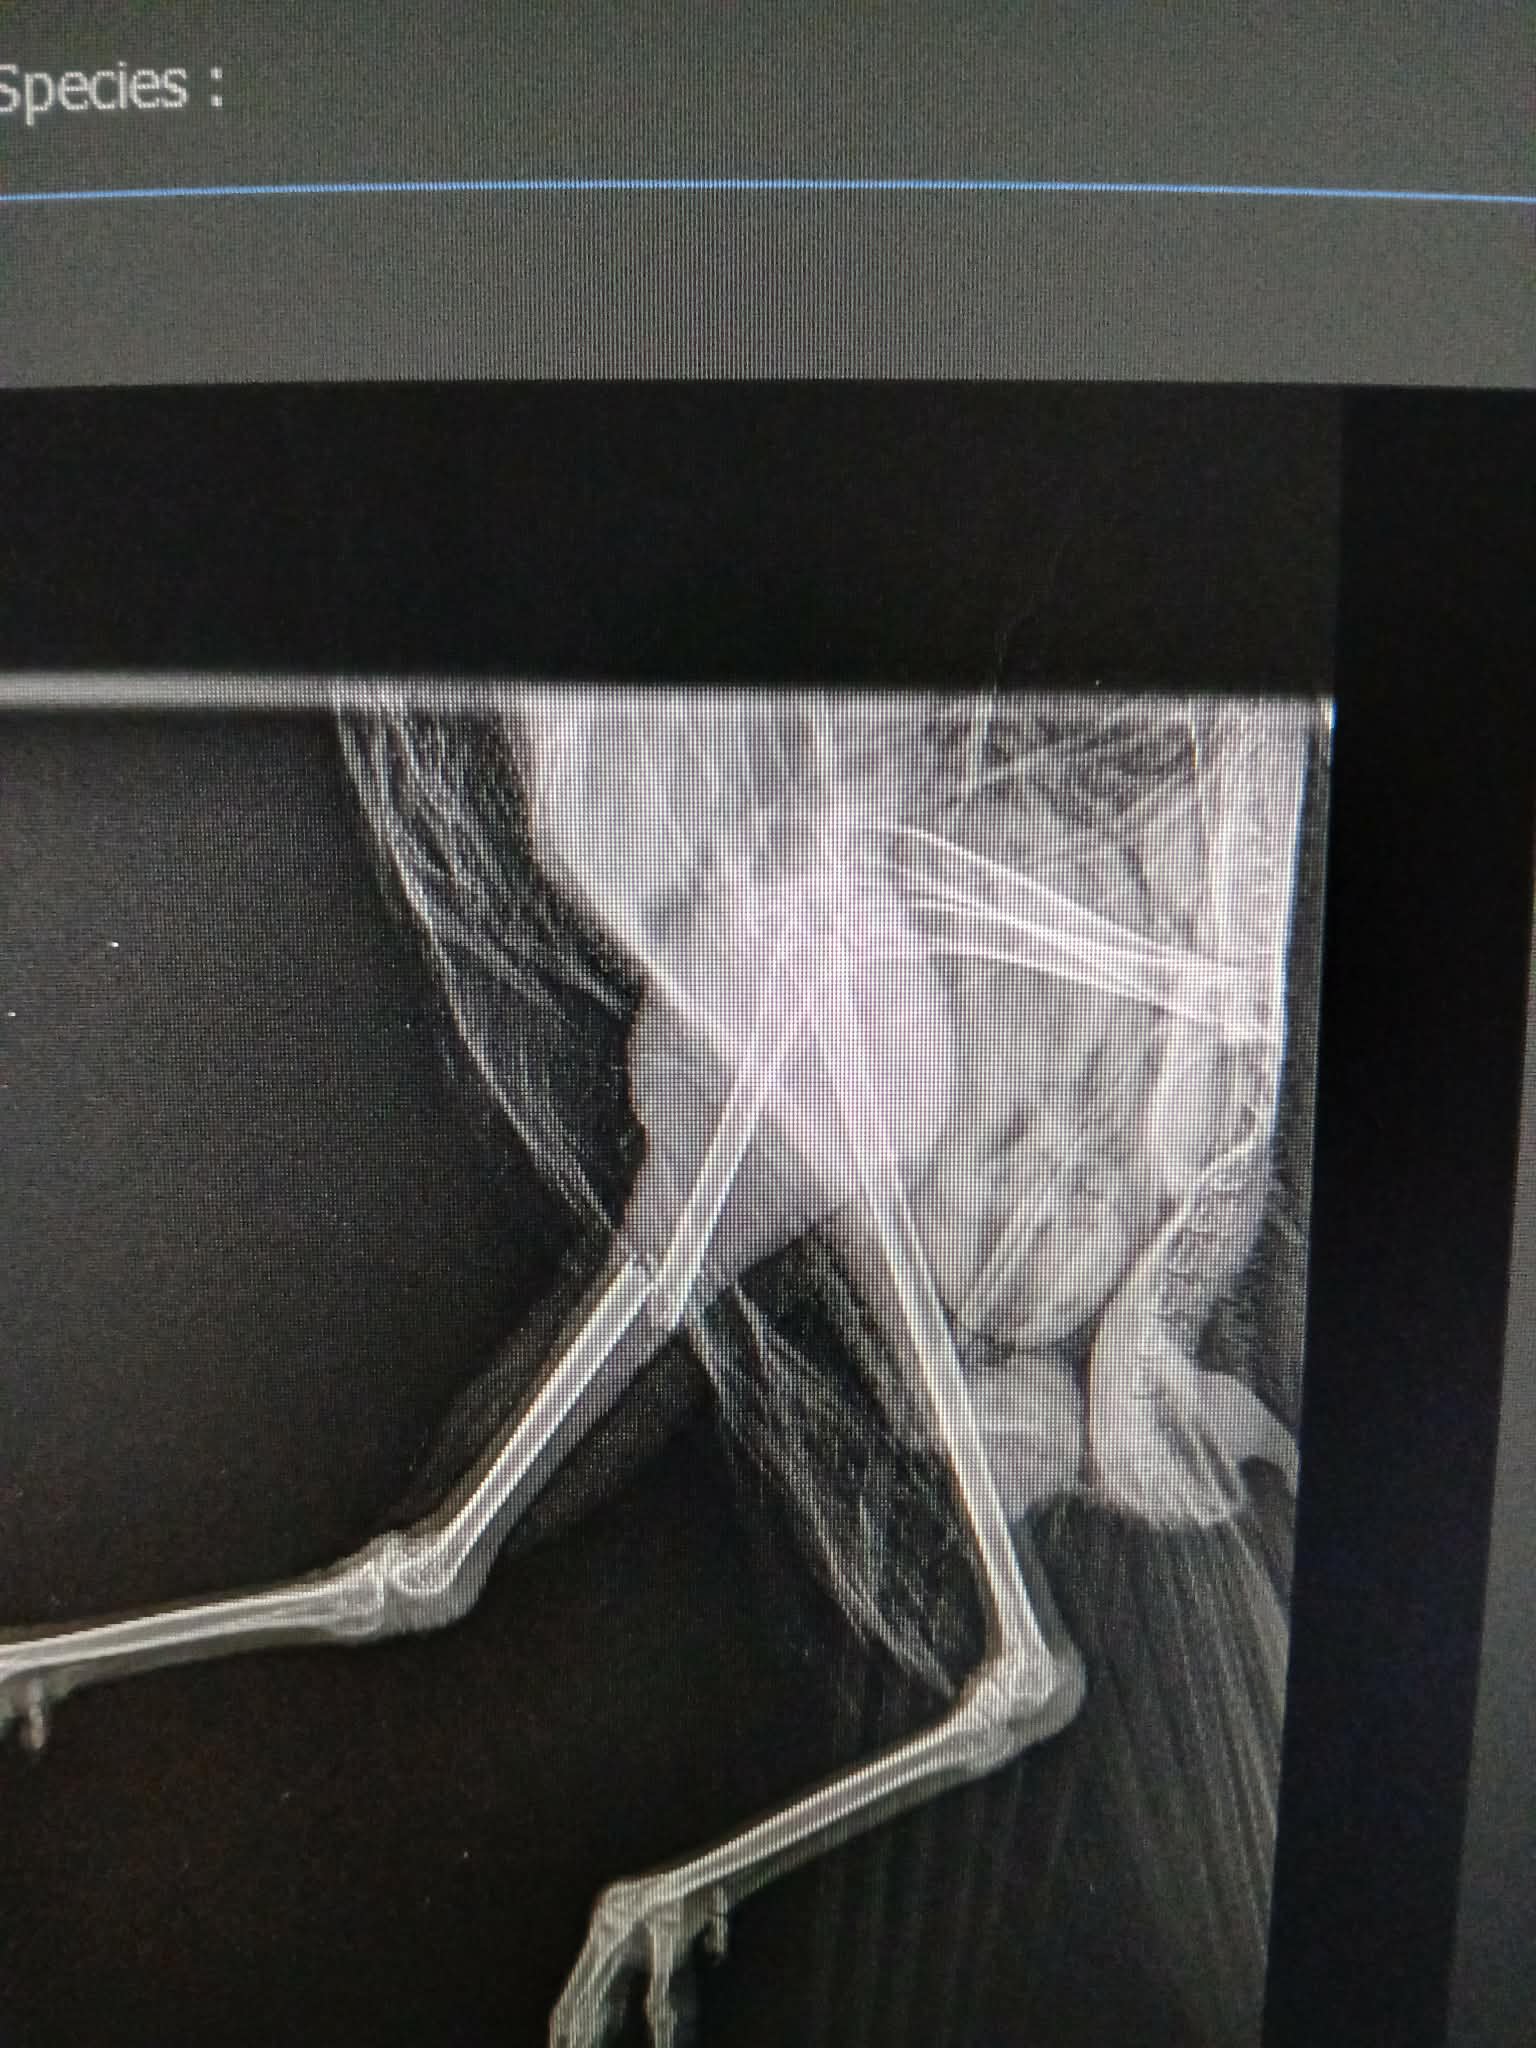

A friend of mine who is a vet nurse found an injured gull by the side of the road near Forfar last Thursday. An x-ray on Friday revealed a closed, mid-shaft fracture which explains why the bird couldn’t walk or stand.

The bird who we have called Piper is an adult weighing 1.5kg and is eating and drinking well. She’s been getting pain relief for the fracture and we had some advice from a veterinarian at a wildlife hospital in Somerset that this is a perfect candidate for an IM (intramedullary) pin.